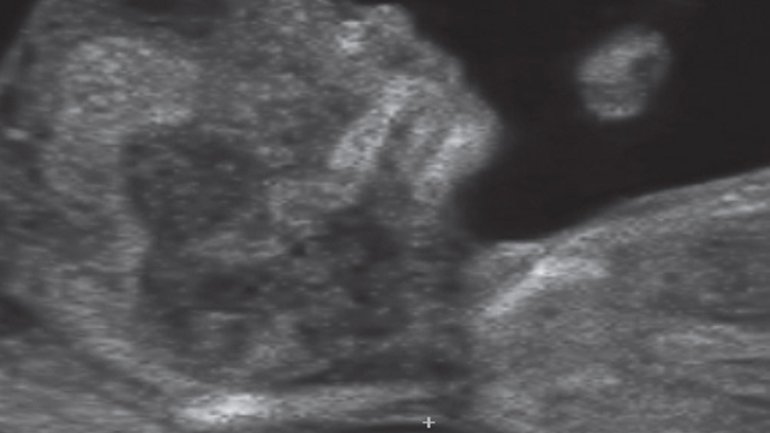

Ultraschall 27. SSW

Mit dem Dopplerultraschall kann auch der Blutfluss in den Blutgefäßen im Gehirn farbig dargestellt werden. Der*die Arzt*Ärztin überprüft so Reifung und Durchblutung des Gehirns und kann darüber bestimmte Krankheiten erkennen oder ausschließen.